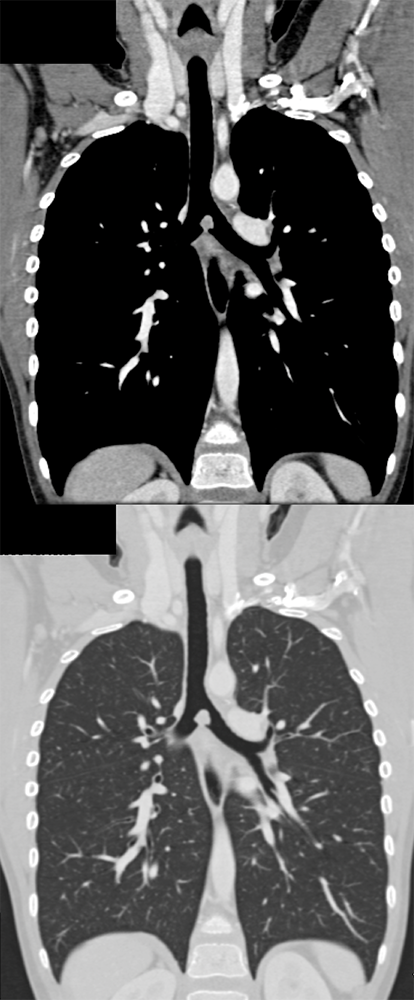

Cough and Hemoptysis ![]() |